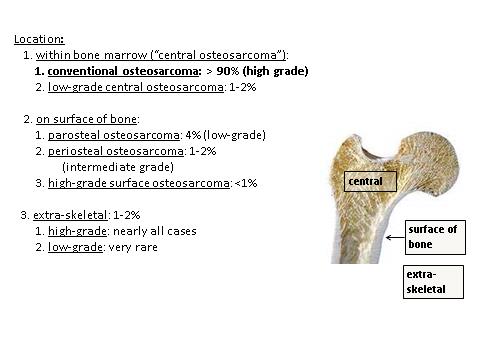

- See Diagrams / tables

- See Diagrams / tables